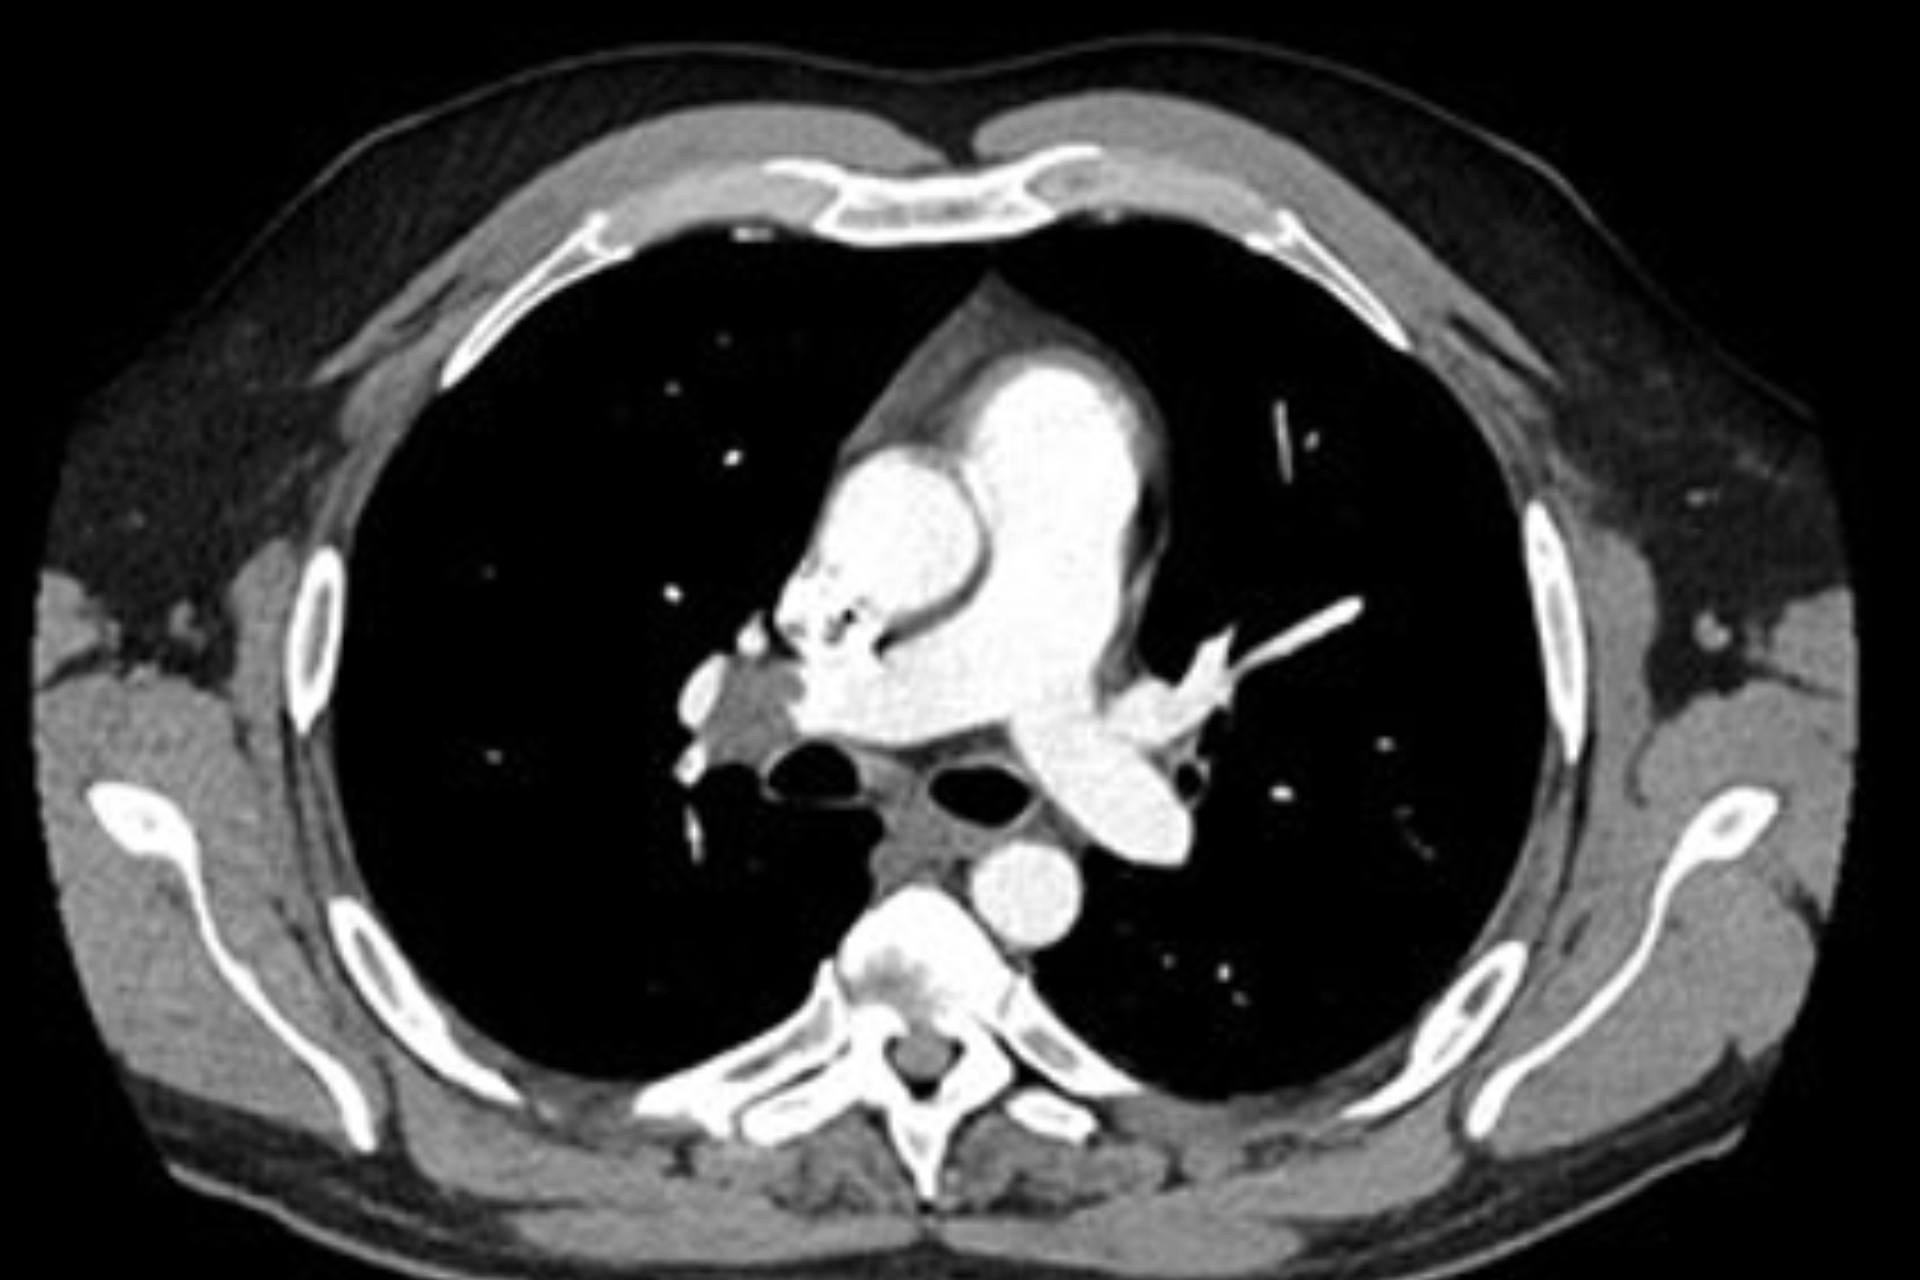

Scanner

Le scanner, aussi appelé tomodensitométrie, est un examen d’imagerie médicale qui utilise les rayons X pour produire des images détaillées en coupes des organes, des os, des tissus mous et des vaisseaux. Rapide, précis et non invasif, il permet d’explorer de n...